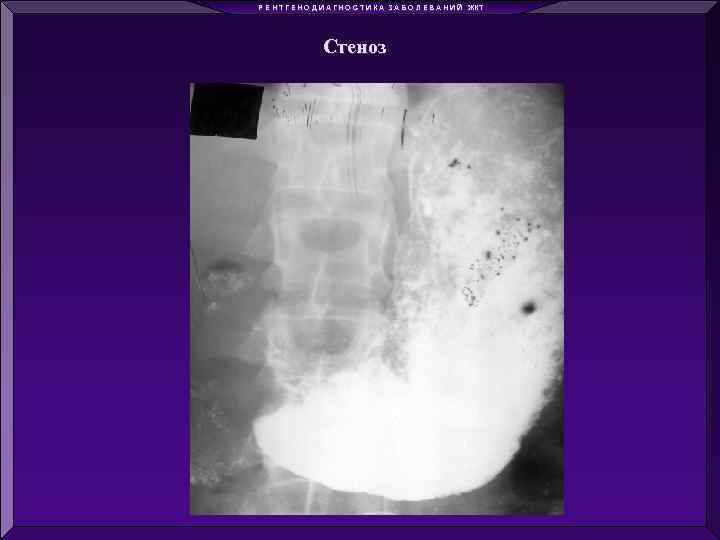

Р Е Н Т Г Е Н О Д И А Г Н О С Т И К А З А Б О Л Е В А Н И Й ЖКТ Стеноз

Р Е Н Т Г Е Н О Д И А Г Н О С Т И К А З А Б О Л Е В А Н И Й ЖКТ Стеноз